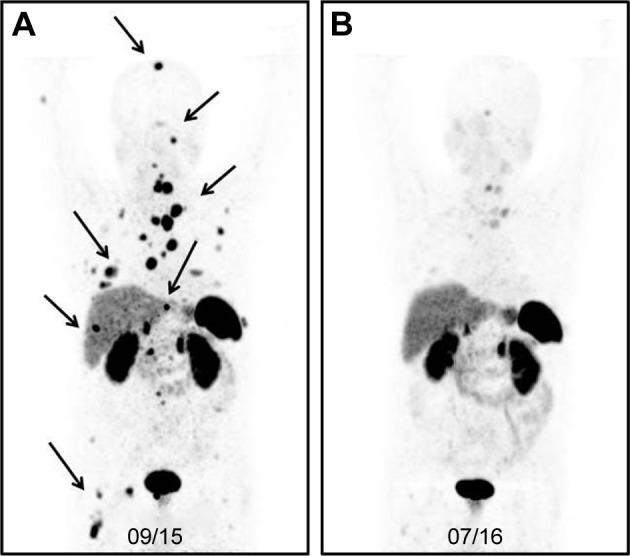

The importance of personalized medicine has been growing, mainly due to a more urgent need to avoid unnecessary and expensive treatments. In nuclear medicine, the theranostic approach is an established tool for specific molecular targeting, both for diagnostics and therapy. The visualization of potential targets can help predict if a patient will benefit from a particular treatment. Thanks to the quick development of radiopharmaceuticals and diagnostic techniques, the use of theranostic agents has been continually increasing. In this article, important milestones of nuclear therapies and diagnostics in the context of theranostics are highlighted. It begins with a well-known radioiodine therapy in patients with thyroid cancer and then progresses through various approaches for the treatment of advanced cancer with targeted therapies. The aim of this review was to provide a summary of background knowledge and current applications, and to identify the advantages of targeted therapies and imaging in nuclear medicine practices.

个性化医疗的重要性一直在不断提高,这主要是因为人们更迫切地需要避免不必要且昂贵的治疗。在核医学中,诊疗一体化方法是一种既定的用于特定分子靶向的工具,可用于诊断和治疗。潜在靶点的可视化有助于预测患者是否会从特定治疗中获益。由于放射性药物和诊断技术的快速发展,诊疗一体化试剂的使用一直在持续增加。在本文中,将重点介绍在诊疗一体化背景下核治疗与诊断的重要里程碑。文章首先介绍了甲状腺癌患者中著名的放射性碘治疗,然后逐步介绍了采用靶向治疗来治疗晚期癌症的各种方法。这篇综述的目的是提供背景知识和当前应用的总结,并确定靶向治疗和成像在核医学实践中的优势。